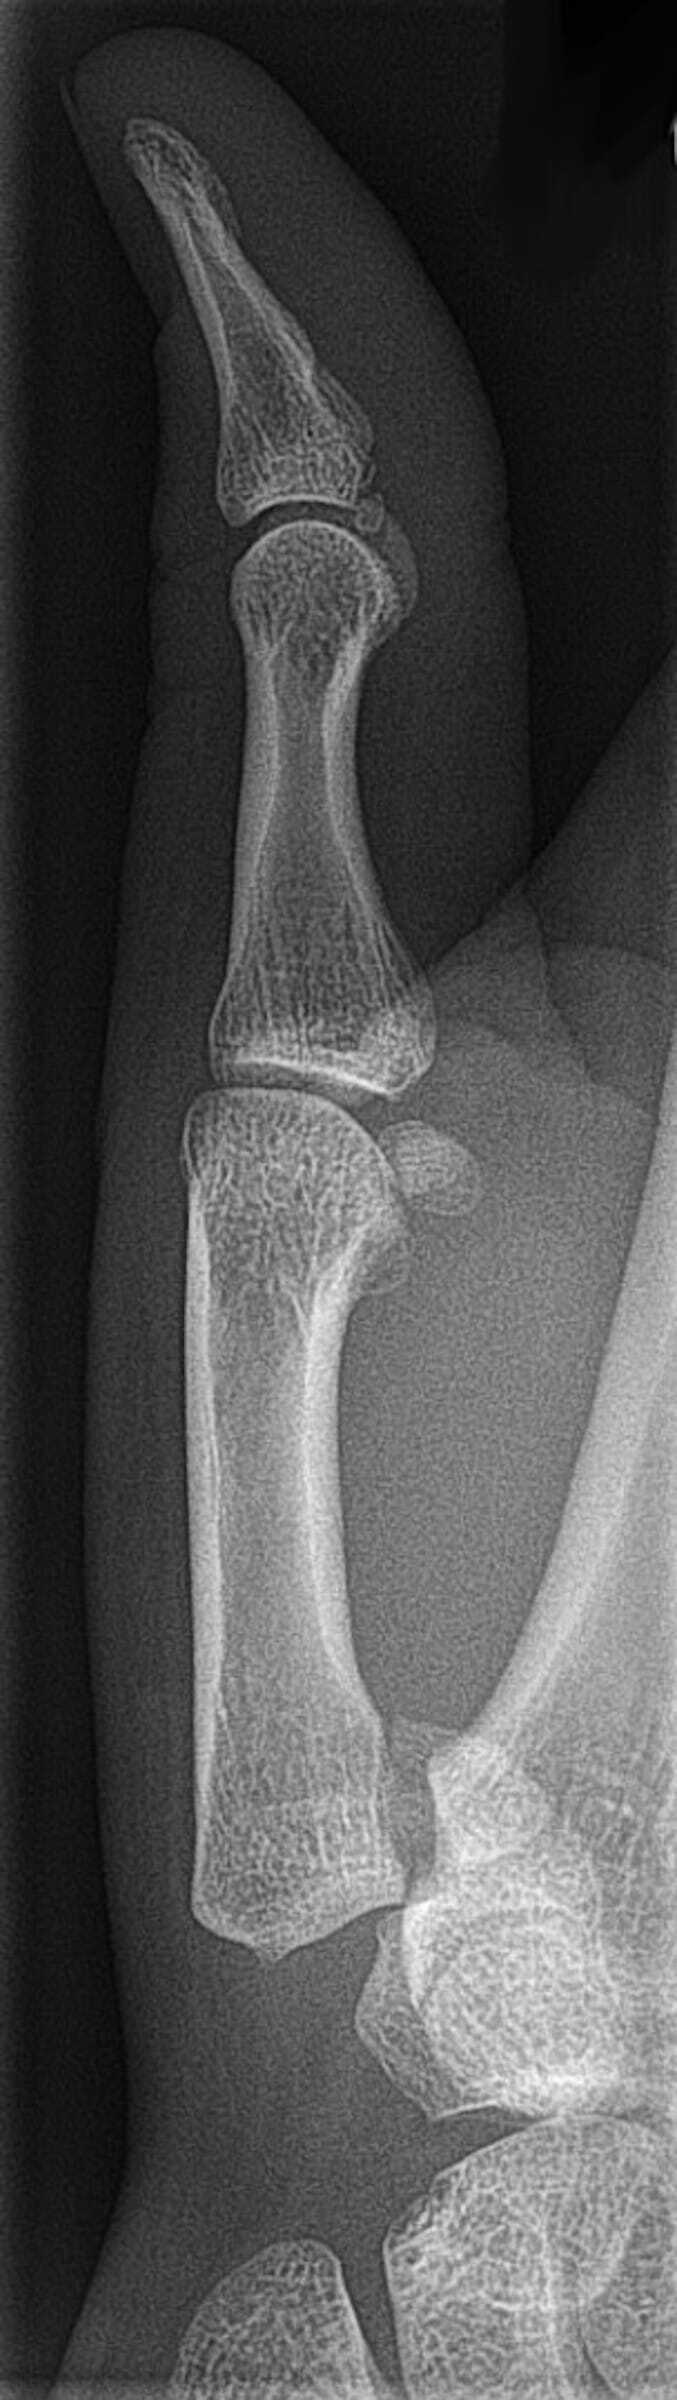

16

Q

vad är en subkapituläär metacaralfraktur?

vilken är vanligast

A

• Den vanligast metakarpalbensfrakturen - Subkapitulärt är benets svagast punkt

• vanligast i V, kallas boxarfraktur

17

vad förutom rtg är viktigt att göra vid metacarpalfraktur?

Kontrollera rotationsfelställning! Syns inte på röntgen, knyt handen, fingrarna ska peka mot scaphoideum och ska inte korsa över något närliggande finger

18

behandling metacarpalfraktur?

• reponera ev

• gips 3v

• kontroll rtg 1v